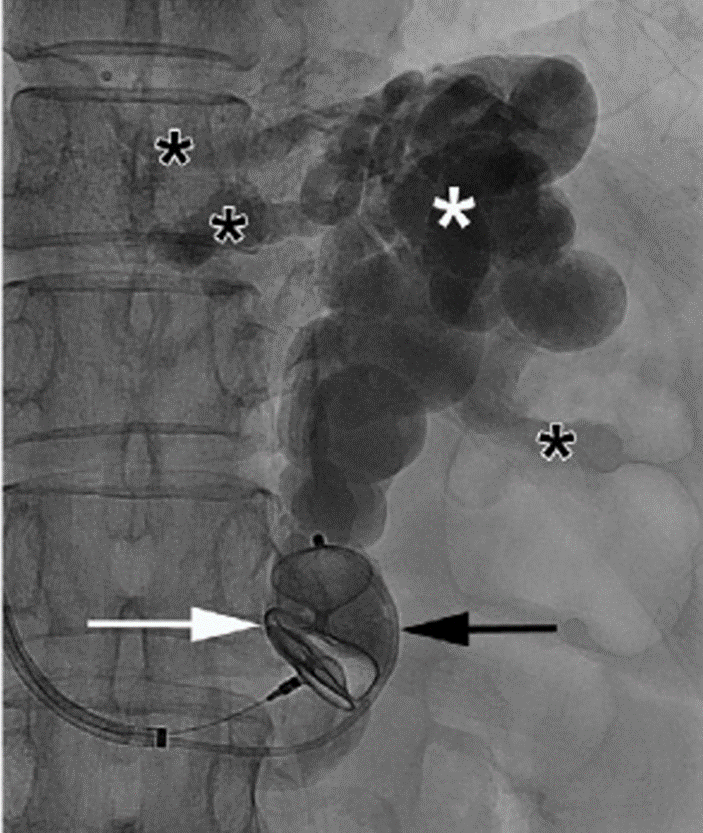

动静脉畸形

冯沅教授:肺动静脉瘘的临床诊疗

陈仁彪教授:血管内介入治疗肺动静脉瘘

图片

使用AVP对于粗大肺动静脉畸形进行栓塞

教你鉴别诊断治疗肺动静脉瘘(PAVM)